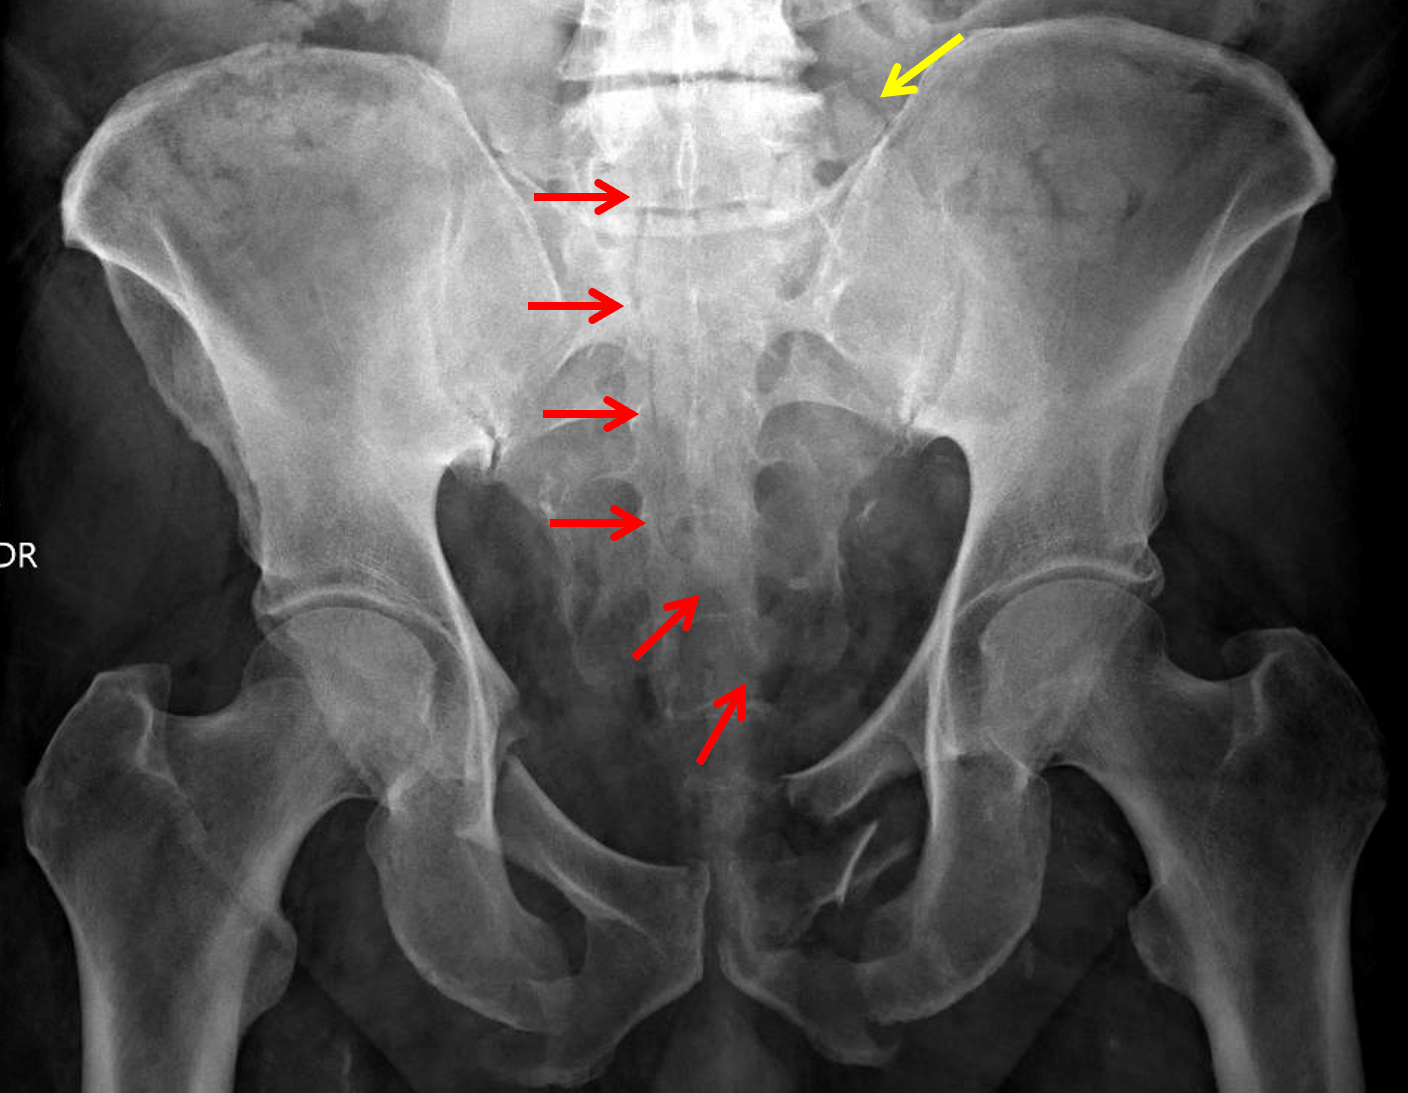

L3 Transverse Process Fracture TrialExhibits Inc.

From radiopaedia.org

Transverse process fracture Image Treatment Transverse Process Fracture A transverse process fracture is typically the result. Here, i will detail the causes, symptoms, how this fracture is diagnosed and finally, how i would treat this type of fracture. Defined as those involving the transverse process only, without extension into the pedicle, lamina, or facet complex. Transverse fractures are a specific type of bone breakage that occurs perpendicular to. Treatment Transverse Process Fracture.

From www.nuemblog.com

transverse process fracture — Ortho Teaching Files — NUEM Blog Treatment Transverse Process Fracture Defined as those involving the transverse process only, without extension into the pedicle, lamina, or facet complex. How are transverse fractures treated? Transverse process fractures are usually treated with a gradual increase in motion, with or without bracing, based on comfort level. Your broken bones need to heal back together. Transverse fractures are a specific type of bone breakage that. Treatment Transverse Process Fracture.